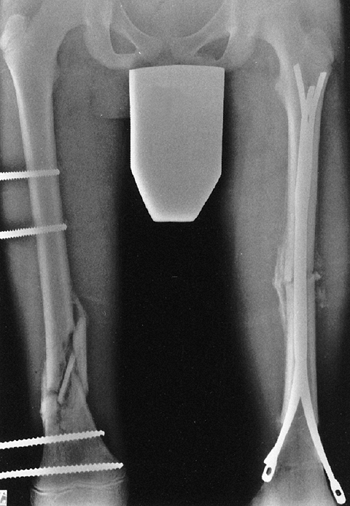

Several classification systems have been proposed since Foucher first

described different types of physeal fractures in 1863 (30). The most widely used classification of physeal fractures is that described by Salter and Harris (31). There are five types of fractures in this classification. Rang has added a sixth that is commonly recognized (Fig. 33.2) (32).

entire growth plate without evidence of a metaphyseal fragment. This

type of fracture is most commonly seen in infants and young children.

The epiphyseal fragment may be nondisplaced or minimally displaced,

making diagnosis difficult. Localized swelling and point tenderness may

confirm the diagnosis. The prognosis for resumption of growth is

excellent with a few notable exceptions, such as physeal separation of

the proximal or distal femur. Partial growth arrest may occur with more

severe trauma, or when periosteum is entrapped in the physis (33,34).

fractures. The fracture line passes through a portion of the growth

plate and exits through a triangular segment of the metaphysis that

remains attached to the intact portion of the growth plate. The

metaphyseal fragment (Thurston Holland fragment) is on the compression

side of the fracture. The prognosis for resumption of growth is

generally excellent, but the risk of growth disturbance varies with the

location of the fracture. Type II fractures of the distal radius rarely

lead to physeal closure (35), but type II fractures of the distal femur cause growth disturbance in approximately 50% of patients (36).

![]() |

|

Figure 33.2 Salter-Harris classification. A: Type I is a transepiphyseal separation without evidence of a metaphyseal fragment. B:

In type II, the fracture line is through the physis, exiting into the metaphysis, leaving a small triangular portion attached to the physeal plate (i.e., Thurston Holland fragment). C: The type III fracture is an intraarticular fracture, with the fracture traversing the physis and exiting through the epiphysis. D: Type IV describes a vertical fracture line that is intraarticular. It passes through the epiphysis, physis, and metaphysis. E: Type V fracture describes a crush injury to the physis that usually is not apparent on initial injury films. F: Type VI fracture is a localized injury to a portion of the perichondrial ring. Subsequent healing produces bone formation across the perimeter of the physis, connecting the metaphysis to the epiphysis. |

a portion of the growth plate, then crosses the epiphysis and the

articular surface. The prognosis for resumption of growth is more

guarded with this injury, and depends on the vascularity of the physis

and damage to the germinal zone. These fractures are more common in

older children in whom growth arrest may not be problematic (29). Anatomic reduction is recommended to reduce the risk of growth arrest and to restore the congruity of the articular surface.

vertically. These fractures are intraarticular and traverse the

epiphysis, physis, and metaphysis. In type IV fractures, a relatively

small proportion of the physes is affected by injury, yet the risk of

growth arrest is high (31). Precise anatomic reduction is recommended to realign the physis and restore the articular surface.

the growth plate. This injury may not be apparent on radiographs

because it does not always involve fracture fragment displacement.

Growth arrest is common. Crush injury to the germinal physeal cells can

occur in combination with other Salter-Harris fracture patterns.

This may result from ligamentous avulsion, direct trauma, burn, or

other forces. Localized growth arrest may occur and lead to asymmetric

growth with angular deformity.